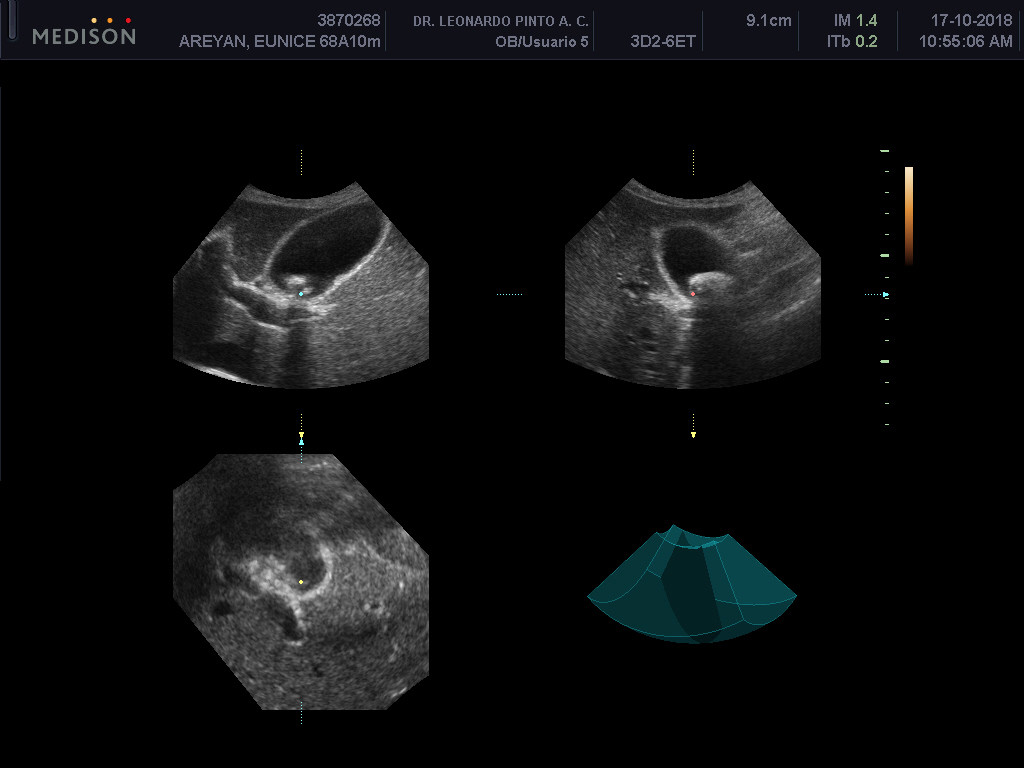

My mother, who is 68 years old, has been diagnosed with a gallstone for which she requires to undergo a cholecystectomy immediately. She’s barely digesting food, so she can’t eat much and she’s been like this for weeks already, so she's getting weaker and losing weight by the day.

Below are the medical informs and exams.